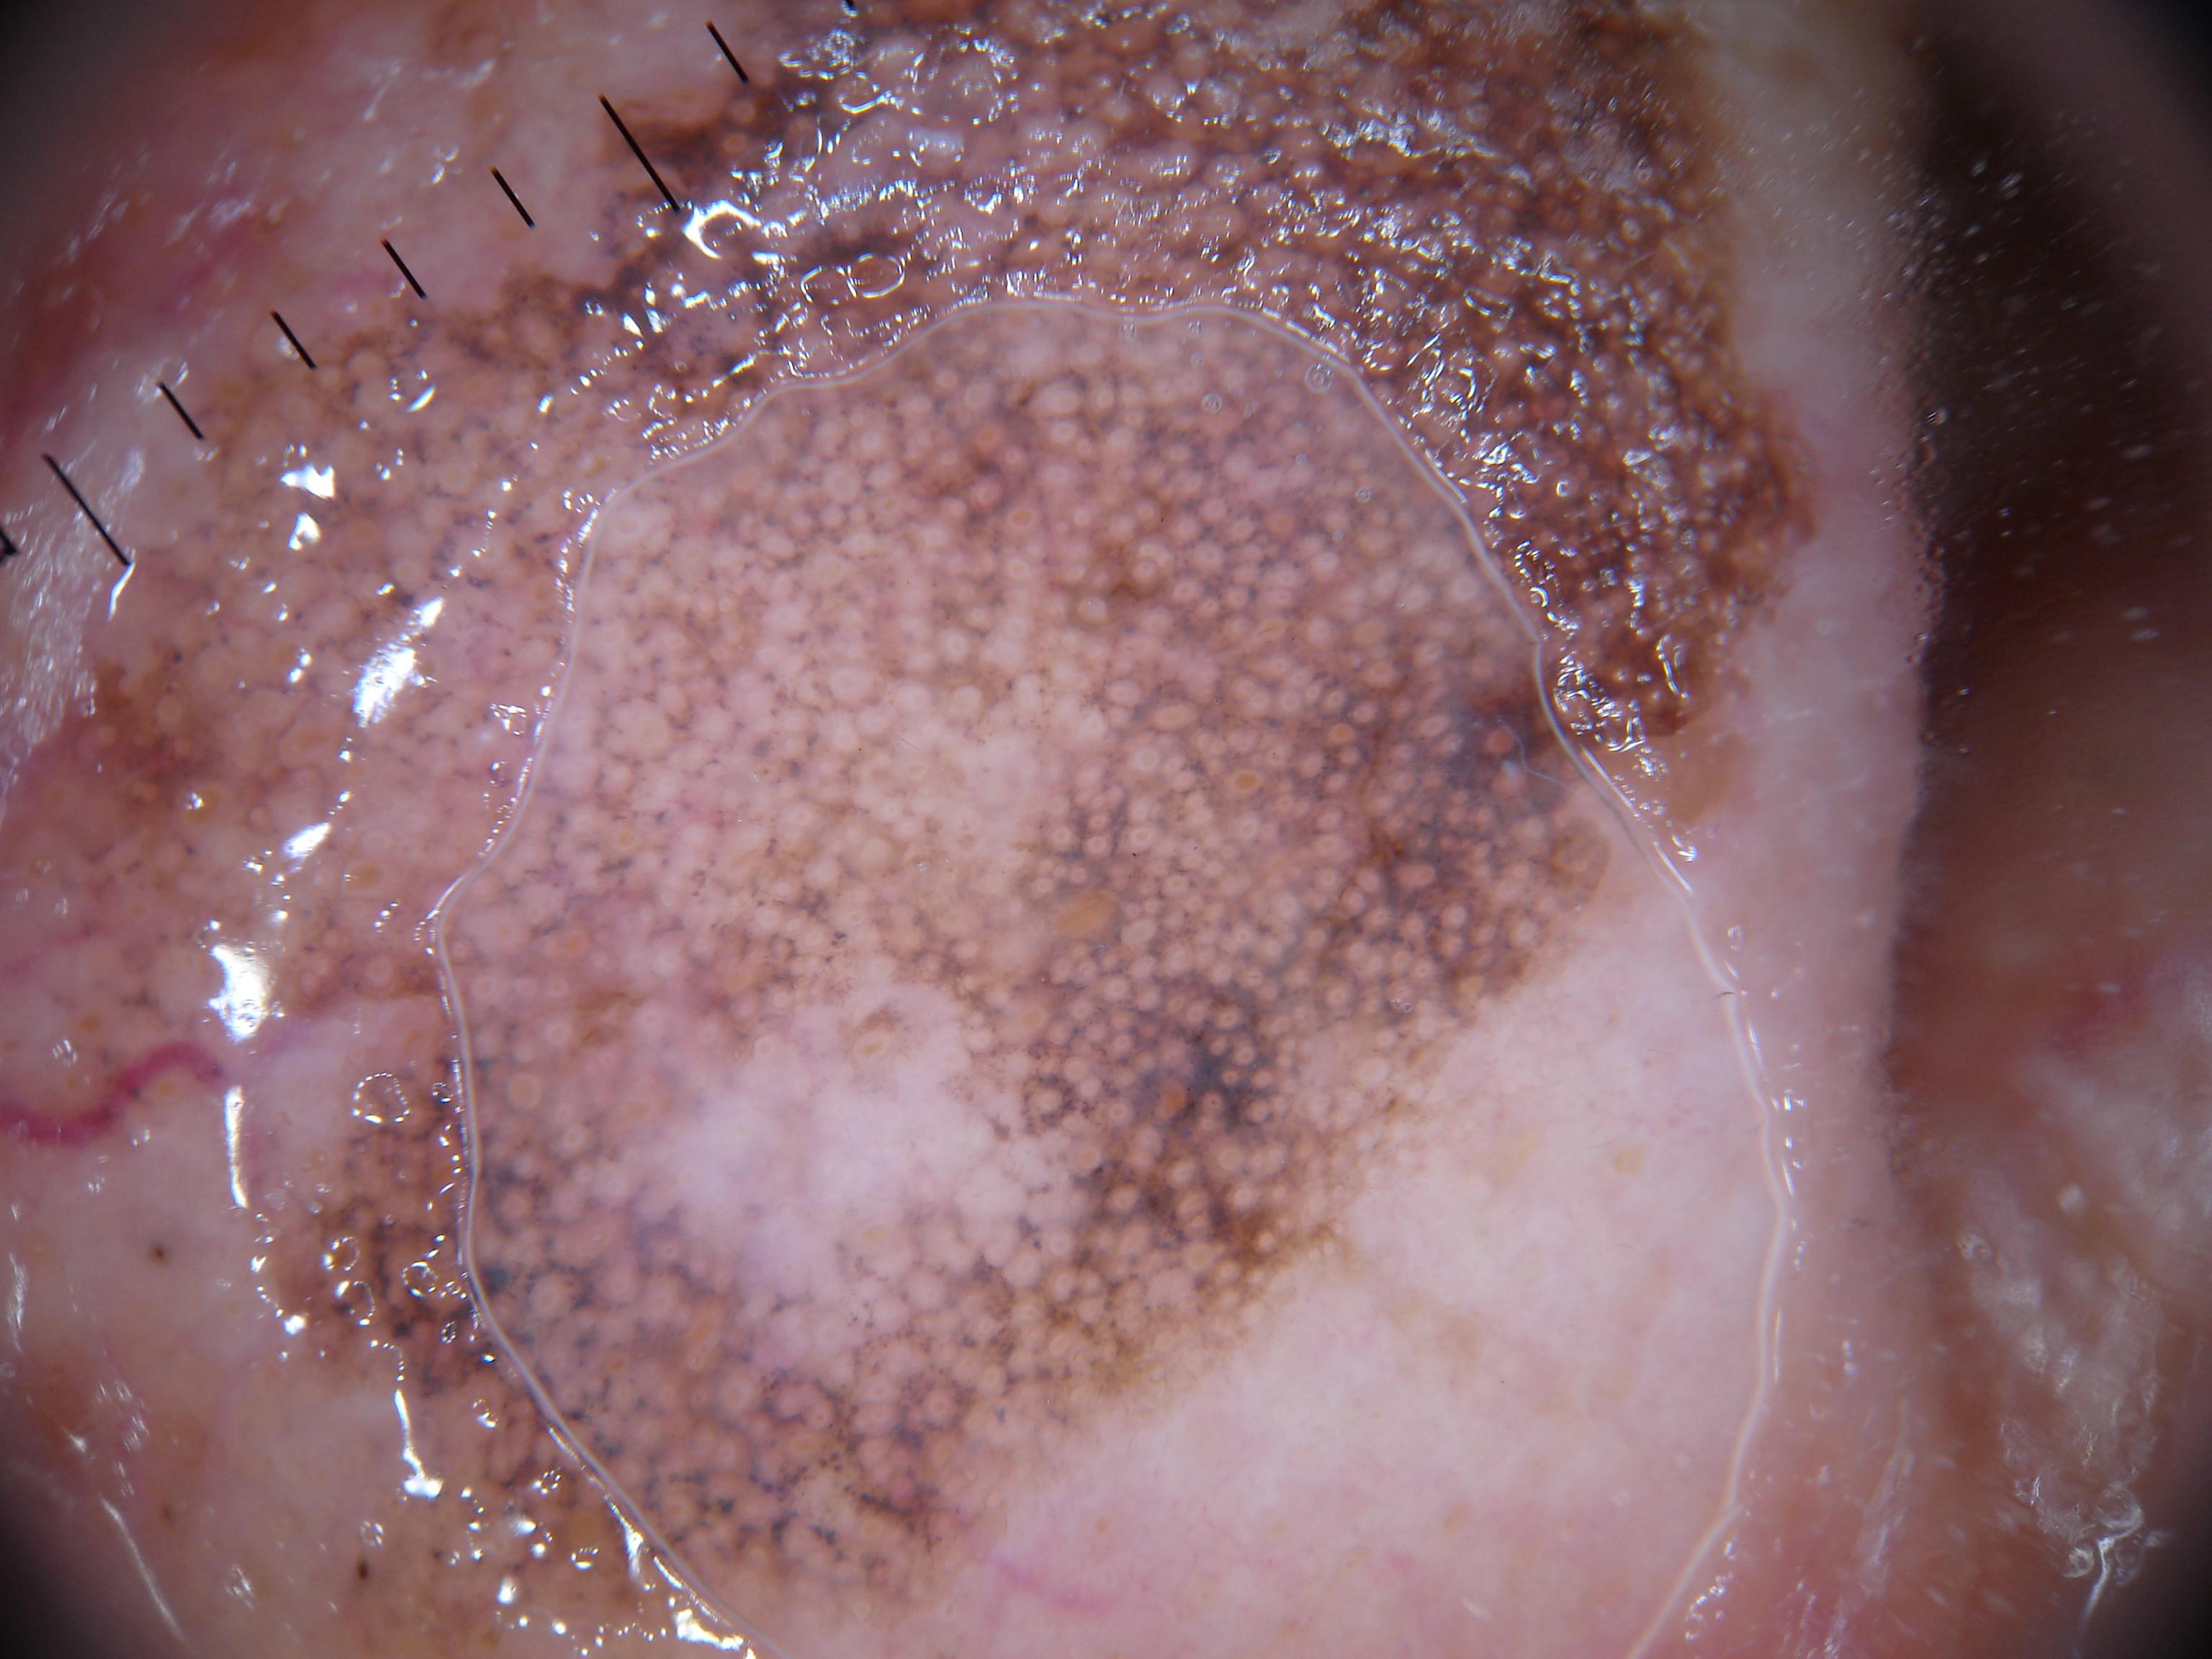

{

"age_approx": 85,

"anatom_site_general": "head/neck",

"concomitant_biopsy": true,

"dermoscopic_type": "contact non-polarized",

"diagnosis_1": "Malignant",

"diagnosis_2": "Malignant epidermal proliferations",

"diagnosis_3": "Squamous cell carcinoma in situ",

"diagnosis_4": "Squamous cell carcinoma in situ, Bowens disease",

"diagnosis_confirm_type": "histopathology",

"family_hx_mm": false,

"image_type": "dermoscopic",

"melanocytic": false,

"patient_id": "IP_9183698",

"personal_hx_mm": false,

"sex": "male"

}